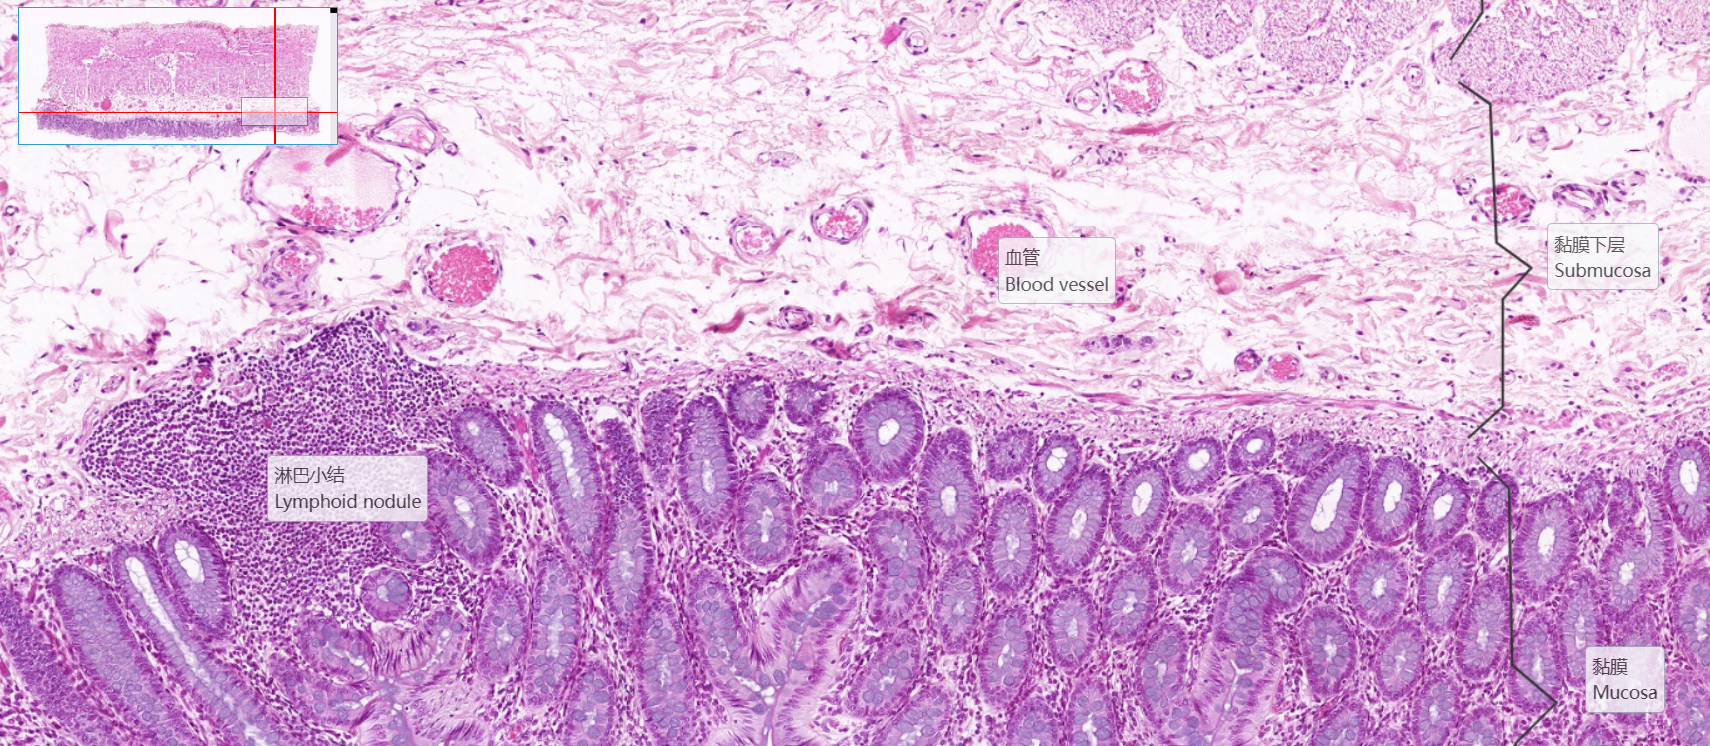

2.结肠腺

3.黏膜下层

4.外膜